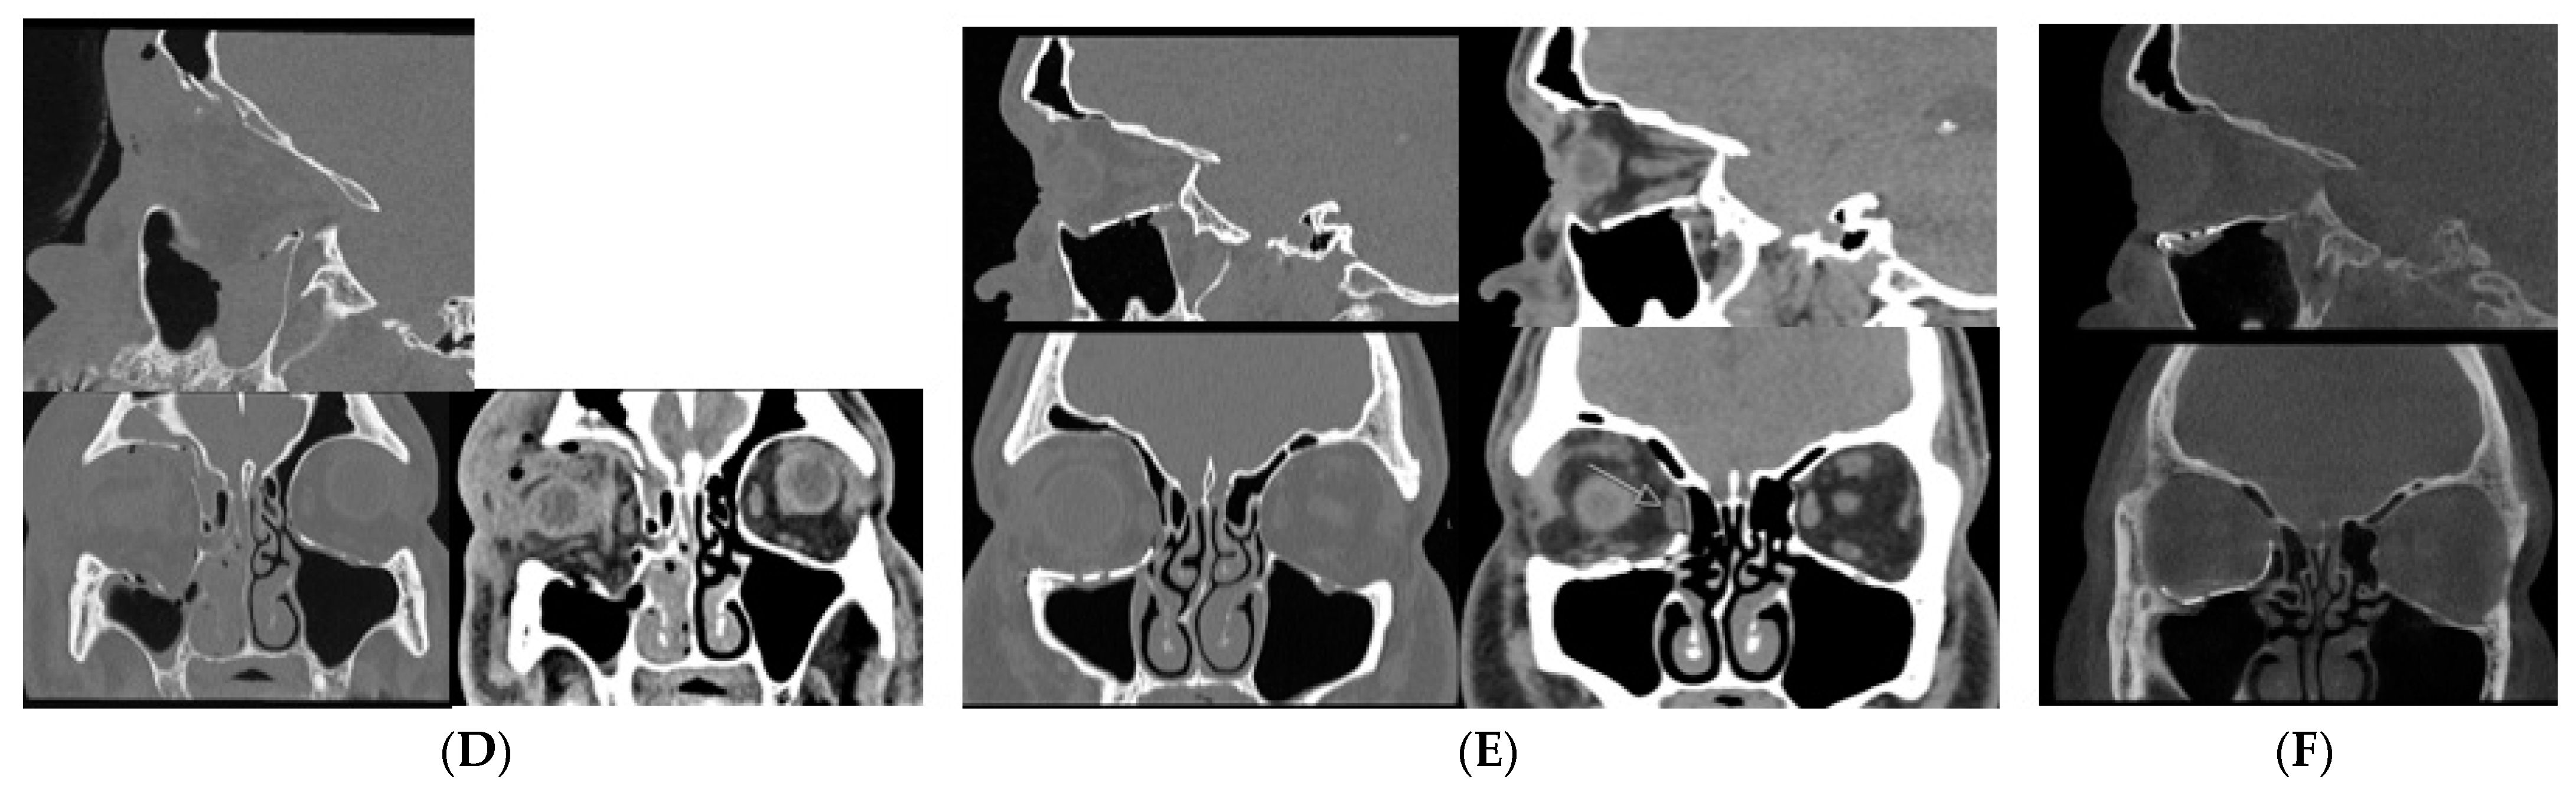

There is insufficient evidence to support the use of CBCT over conventional CT in the acute setting where there are concomitant facial or head injuries or where there is suspicion of muscle entrapment or retrobulbar haemorrhage. Figure 5 shows a CBCT coronal section of a patient with a right orbital floor fracture. The fat and muscle are indistinguishable when compared with the same slice in a conventional CT and therefore are not adequate for assessing muscle entrapment.

Figure 5.

CBCT (A) CT bone window (B) and CT soft tissue window (C) of the same patient, showing a right orbital floor fracture with soft tissue herniation. CT soft tissue windowing allows for differentiation between fat and muscle. On CBCT fat and muscle are indistinguishable. CBCT is suitable for assessment of the bony injury, but it is not possible to assess for muscle entrapment on CBCT. CT (D) at time of acute orbital trauma shows a right orbital fracture involving the floor, medial wall, and orbital roof. Soft tissue windows show inferior and medial rectus herniation. CT (E) prior to revision orbital floor repair shows that the medial rectus is herniating into a persistent medial wall defect (see arrow). CBCT (F) post-revision orbital floor repair shows that the new custom plate is well positioned with repair of both the floor and medial wall.

In the outpatient setting, in the absence of eye signs and a conventional CT, CBCT may be adequate for assessing the size of the defect and orbital volume in surgical planning. Furthermore, in this setting, mirror computational planning can be used and patient-specific implant (PSI) adapted free-hand on 3D-printed models. In the majority of cases, PSIs are acquired from conventional CT data. However, studies have shown the feasibility of using CBCT to construct orbital PSI [44]. At the time of publication, CBCT scans were not accepted for PEEKMilled implants, Titanium 3D-printed orbital and cranial implants by some medical technology companies (Synthes CMF CT-CBCT Scan Protocol) [45]. In our unit, CBCT is frequently utilised to assess the adequacy of orbital reconstruction (Figure 5).